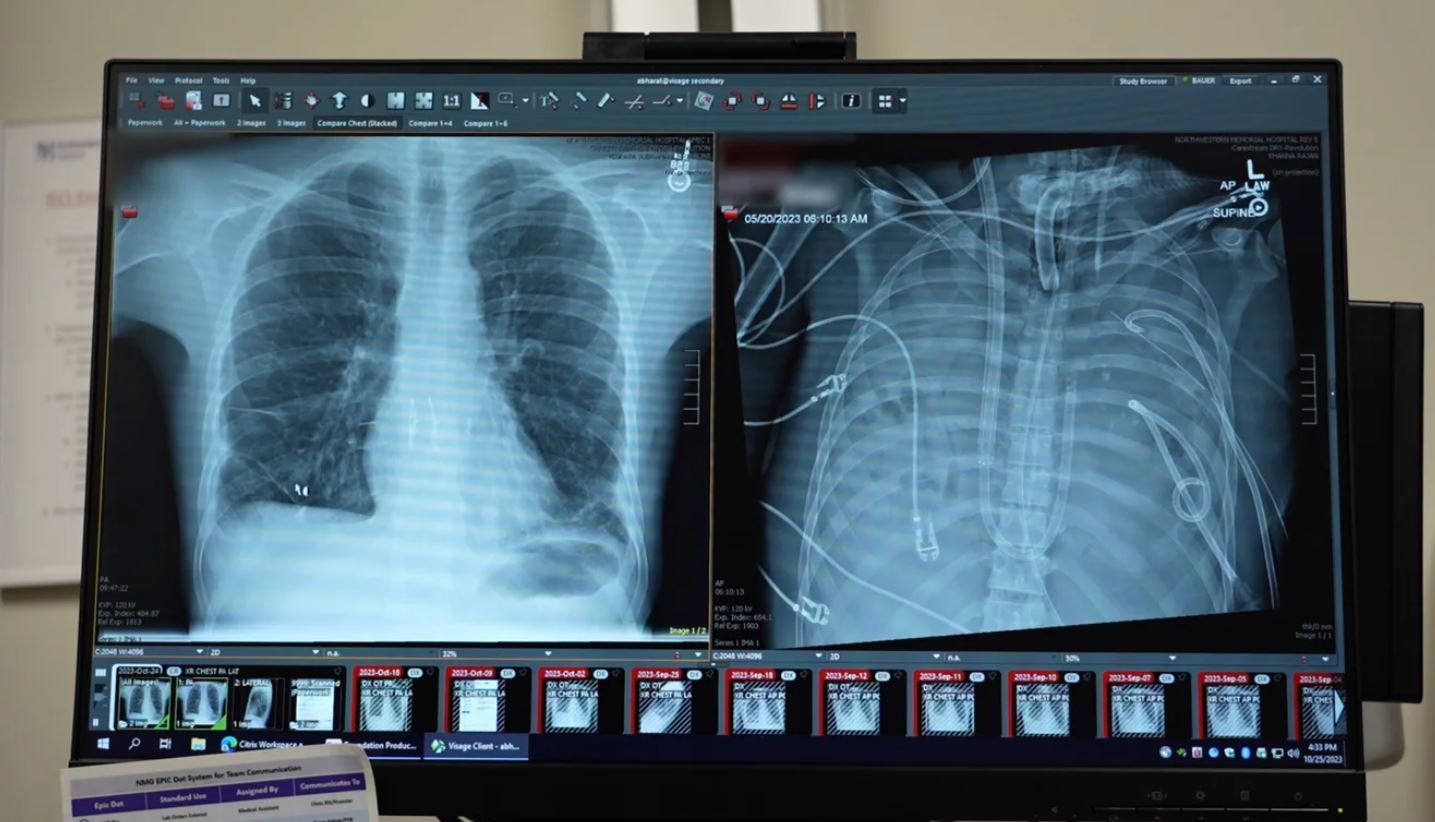

Chú thích ảnh

Hình ảnh bên trái cho thấy phổi mới (được cấy ghép vào bệnh nhân sau khi ông được duy trì sự sống bằng phổi nhân tạo) đặt cạnh phổi cũ của ông (bên phải). Ảnh: Northwestern Medicine